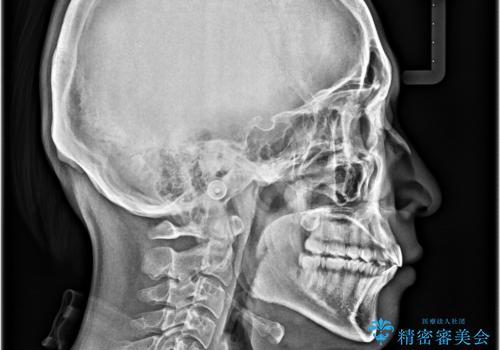

- 上下前歯の捻れやデコボコを気にして来院された患者様です。

マウスピース矯正でもワイヤー矯正でも対応可能でしたが、極力楽をして治したいとのことでワイヤー装置にて治療をおこなうこととしました。

口元はそれほど突出しておらず、患者様自身も気にしていらっしゃいませんでしたが、前歯の捻れやデコボコを解消すると、前方に拡大され、治療後に出っ歯仕上がりとなるリスクがあったため、補助装置により上顎臼歯を後方移動していくこととしました。